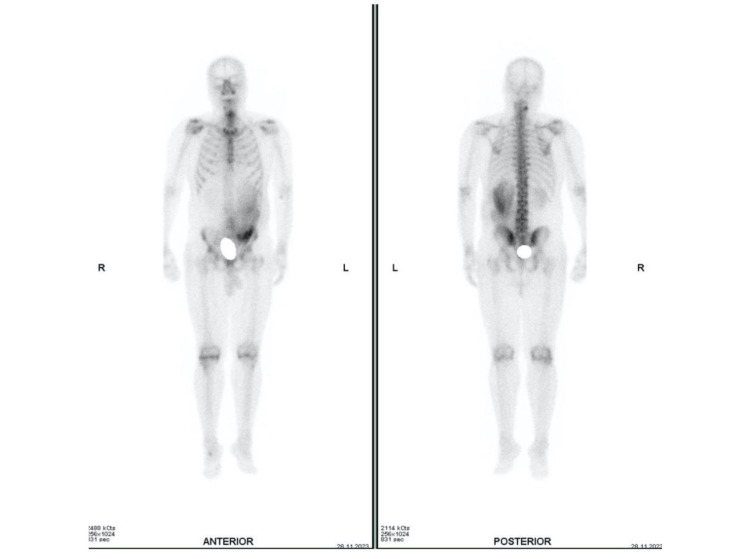

一位患有膀胱癌的62岁男性患者被转介到我们的机构进行锝-99m亚甲基二膦酸盐骨显像以评估骨转移。虽然骨扫描未显示异常摄取,但全身扫描在左侧肾周和骨盆区域检测到骨外摄取。计算机断层扫描显示穹窿破裂,示踪剂在肾周聚集。我们的诊断非常一致,并以经皮引流术治疗肾周尿漏的治疗态度为导向。

A 62-year-old male patient, with bladder carcinoma, was referred to our institution for Technetium-99m methylene diphosphonate bone scintigraphy to assess for bone metastasis. While the bone scan showed no abnormal uptake, extraosseous uptake was detected in the left perirenal and pelvic regions on the whole body scan. Computed tomography showed fornix rupture and demonstrated tracer pooling in the perirenal collection. Our diagnosis was very consistent, and oriented the therapeutic attitude towards a percutaneous drainage for the perinephric urinary leak.